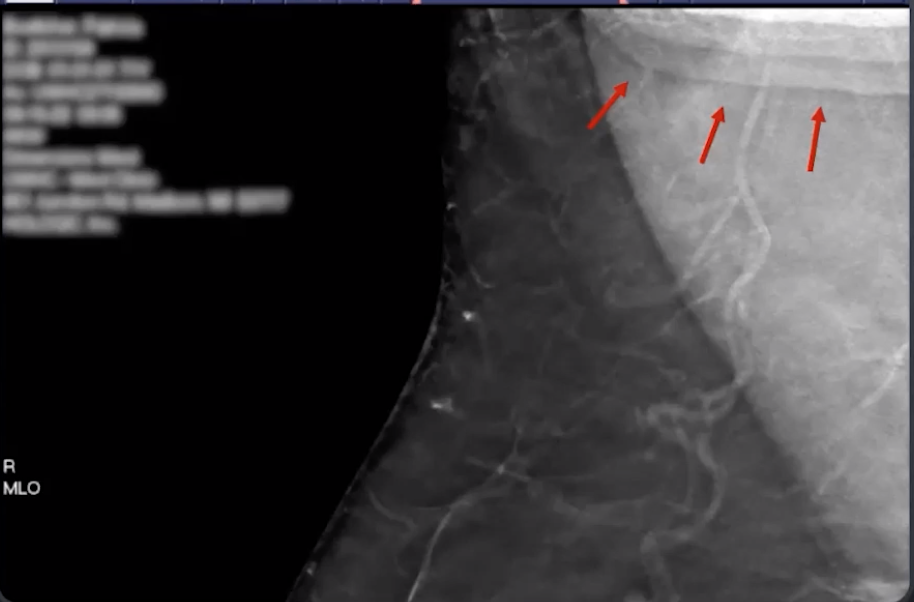

Stair-Step & Bright Line Artifacts

• Type of truncation artifact

• Stair step-Artifact

• Tissue or object outside the margin of detector is captured by wide angle projections

• Basically something is in the way of your boob and is seen in the picture when you don’t want it to it seems

• Bright line artifact

• When stair-step artifact is reconstructed into synthesized mammogram and appears as a bright line